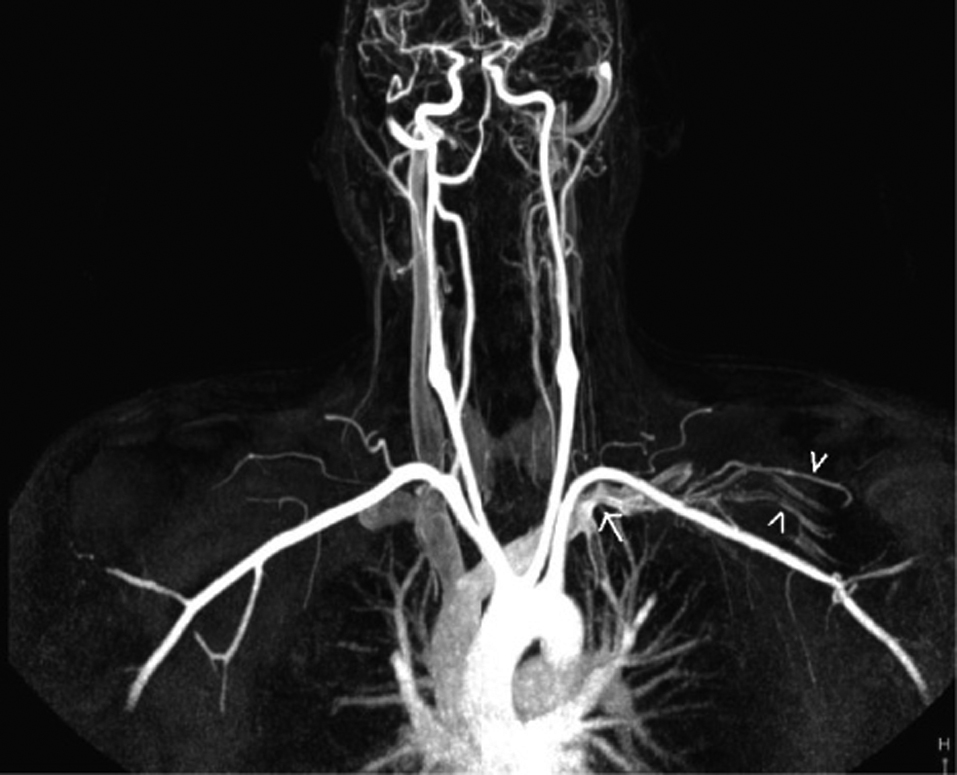

A 42-year-old male presented with pain and swelling of the left arm after a sequence of intense, repetitive weightlifting exercises. Upon questioning, he disclosed that he had been engaged with weightlifting for a long time and had complaints for a while. His medical history was unremarkable. Laboratory tests were positive for antithrombin 3 and factor leiden, agents that facilitate coagulation. Based on these findings, upper-extremity effort thrombosis was suspected. Thereafter, contrast enhanced upper-extremity venous MR angiography (MRA) and color Doppler US (CDUS) were performed to verify the diagnosis. Contrast-enhanced MRA revealed near-complete occlusion of the proximal left subclavian vein and distal collateral formations (Fig. 1). CDUS showed a heterogeneous thrombotic mass that filled almost the entire proximal segment of the left subclavian vein (Fig. 2). Thrombosis extended into the proximal segment of the left internal jugular vein (IJV) (Fig. 3). Furthermore, extensive venous collateral formations were presented in the left proximal cervical localization (Fig. 4). Both MR angiographic and sonographic findings were consistent with PSS.

![]() Click for large image | Figure 1. Coronal maximum-intensity-projection contrast-enhanced MR angiogram obtained after left antecubital vein injection reveals near-complet occlusion of the left proksimal subclavian vein (arrow) and distal venous collaterals( arrowhead). |